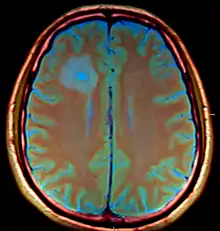

يتم تشخيص المرض عن طريق إجراء فحص بالأشعة المقطعية أو بالتصوير المقطعي المحوسب (CT) باستخدام صبغة التباين، وفي المرحلة الأولى من الالتهاب، والتي يُشار إليها باسم التهاب الدماغ، لا يأخذ التقرحُ الأوليّ الشكل الغشائيّ الشبيه بالكبسولة بحيث قد يصبح من الصعب التمييز بينه وبين التقرحات الأخرى أو احتشاء المخ، وفي غضون من أربعة إلى خمسة أيامٍ، يبدأ الجسم في تكوين غشاءٍ كبسوليّ حول مكان الالتهاب والنسيج الدماغيّ التالف المصاحب له، وهو الأمر الذي يعطي التقرح شكل الحلقة المضيئة المميز على صورة الأشعة المقطعية باستخدام الصبغة (وذلك لأن المادة الصبغية التي يتم حقنها عن طريق الوريد لا تستطيع اختراق ذلك الغشاء الكبسوليّ، وبالتالي تقوم بالتجمع حول التقرح داكن اللون على شكل حلقةٍ منيرة)، كما يحظر اتباع إجراء البزل القطني في هذه الحالة (كما هو الحال في التقرحات المنتشرة في المخ) على الرغم من اتباعه في تشخيص العديد من الأمراض المعدية التي تصيب الجهاز العصبيّ المركزيّ؛ وذلك لأن إزالة قدرٍ معين من السائل الدماغيّ الشوكيّ قد تؤدي إلى تغير توازنات الضغط المحددة داخل القحف مسفرةً عن نقل أو إزاحة أنسجة المخ داخل الجمجمة فيما يعرف باسم انفتاق الدماغ.

وقد تظهر الحلقة المنيرة أيضًا في صور الأشعة الخاصة بحالات النزف الدماغيّ وأورام المخ، إلا أنه في حال وجود ارتفاعٍ مفرطٍ وسريع في درجة الحرارة ونتائج الفحص العصبي البؤري (كالخَزَل الشِقِّيّ والشعور بالحبسة، إلخ) وعلامات زيادة الضغط داخل القحف، فإن التشخيص الأكثر احتمالاً هو الإصابة بخُرَّاج المخ.